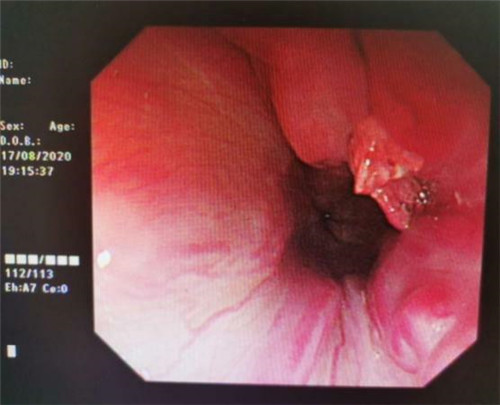

手术中,在镜下发现数条食管静脉曲张延伸至胃底,胃腔内有大量新鲜红色血液及血凝块,寻找到出血部位时仍在向外渗血,血压持续下降,患者时刻有生命危险。曹鹏副主任当机立断对曲张静脉破口处进行组织粘合剂及硬化剂注射,并对曲张静脉进行套扎治疗,在麻醉师陈琦的保驾护航下,整个过程不到半个小时,为患者成功止血,患者转危为安。